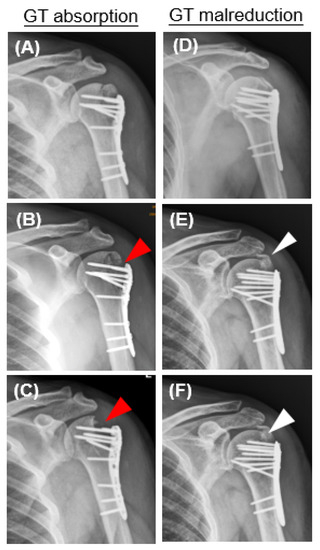

| Greater tuberosity resorption | 13/94 (13.82%) |

| Malreduction of greater tuberosity | 11/94 (11.7%) |

| Time from surgery to GT resorption or malreduction (week) | 8.77 ± 7.86 |